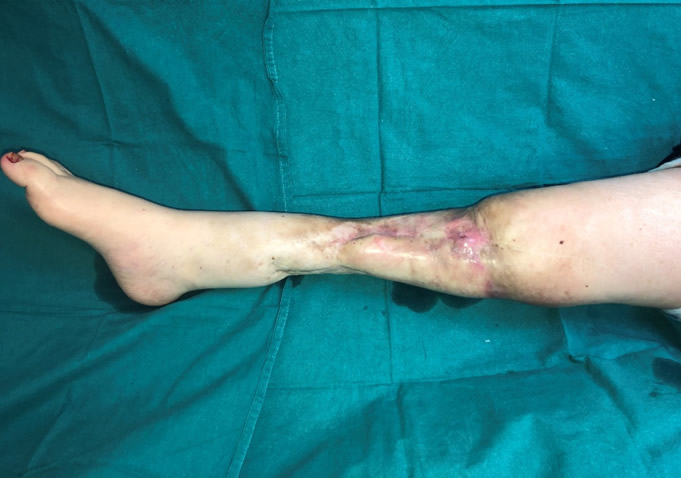

Diagnóstico: Prótesis oncológica de rodilla infectada y expuesta

Paciente de 41 años con antecedentes de osteosarcoma de rodilla previamente intervenida con una prótesis oncológica. La prótesis está infectada, expuesta y en una extremidad lesionada por la radioterapia. La amputación es el único tratamiento que le han recomendado.

- Megaprótesis oncológica de rodilla infectada

- Defecto masivo articular con exposición de la prótesis

- Contraindicación de recambio protésico

03. Resultado

El resultado funcional fue excelente con preservación de la pierna. La paciente pudo caminar a los 20 meses de la intervención. Una técnica única desarrollada por el Dr. Cavadas que permite evitar la amputación en casos extremos de prótesis oncológica infectada.